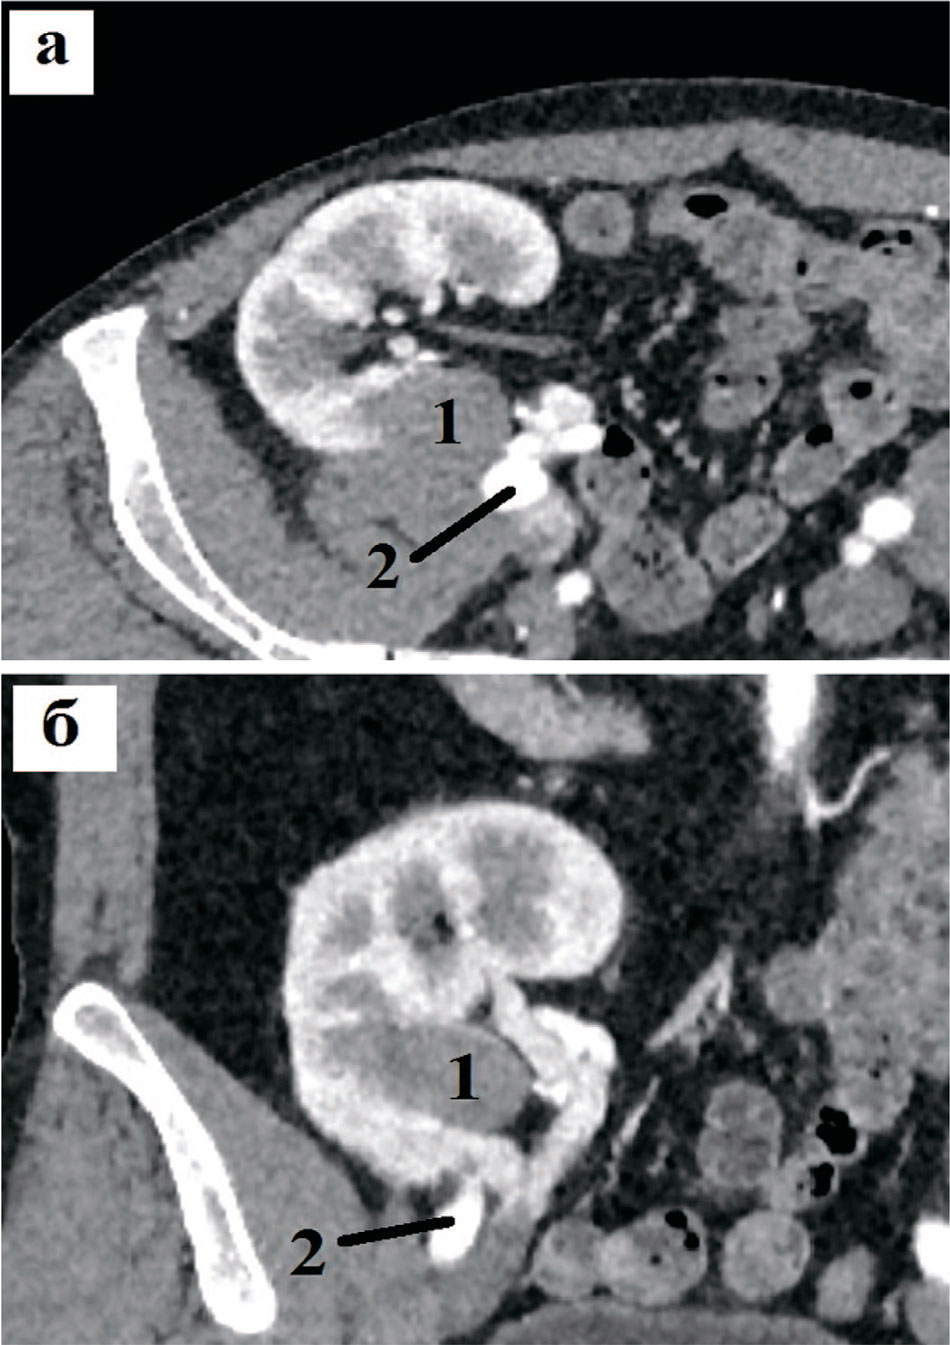

Рис. 4. Компьютерные томограммы пациента с образованием трансплантированной почки (критерий N): а – аксиальная проекция, б – коронарная проекция. Близость опухоли (1) к подвздошным сосудам (2)

Fig. 4. Computer tomograms of a patient with a formation of a transplanted kidney (criterion N): a – axial projection, b – coronal projection. Proximity of the tumor (1) to the iliac vessels (2)

Минимальное расстояние от опухоли до ЧЛС ТП составляет 0,2 см, что соответствует 3 баллам по шкале R.E.N.A.L. и 2 баллам – по шкале R.E.N.A.L.ТК (рис. 3). По второму параметру критерия N модифицированной шкалы, характеризующему близость к подвздошным сосудам, данная опухоль имеет 2 балла, так как непосредственно прилегает к данным сосудам и, соответственно, имеет расстояние менее 5 мм (рис. 4). Таким образом, опухоль имеет максимальный балл по критерию N модифицированной шкалы, равный 4.